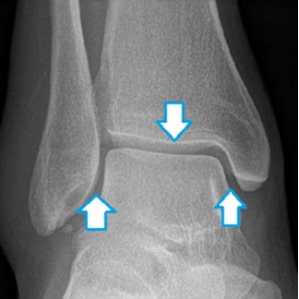

• Рентгенографические признаки разрыва дельтовидной связки:

о Ширина медиального свободного пространства превышает 4 мм:

- Значения 4-6 мм являются пограничными

о Латеральное смещение купола таранной кости

• Признаки разрыва межберцового синдесмоза:

о Величина перекрытия большеберцовой и малоберцовой костей о Смещение малоберцовой кости из малоберцовой вырезки большеберцовой кости